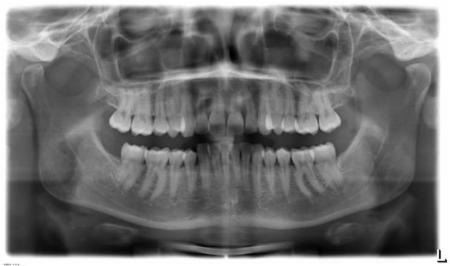

2.) Das Orthopantomogramm (OPG) oder auch Panorama-Übersichtsaufnahme zeigt den Stand des Zahnwechsels, die Zahnanlagen im Kiefer, Fehlbildungen der Zähne, den Zustand der Zahnwurzeln und des Zahnhalteapparates (Parodont).

Insbesondere beim Wechselgebiss gibt das Röntgenbild dem Zahnarzt und Kieferorthopäden die erforderlichen Informationen über die Anlage und Lage von Zähnen sowie den Entwicklungsstand der Wurzelbildung. Hier können auch rechtzeitig besondere Befunde wie Nichtanlage von Zähnen, überzählige Zähne und falsch liegende Zähne (Retentionen) entdeckt werden.

Diese Aufnahmen werden während der Behandlung wiederholt, um z.B. den Zahnwechsel zu kontrollieren, die Zahnachsenstellung zu überprüfen und Veränderungen am Zahnhalteapparat und der Zahnwurzel zu sehen.